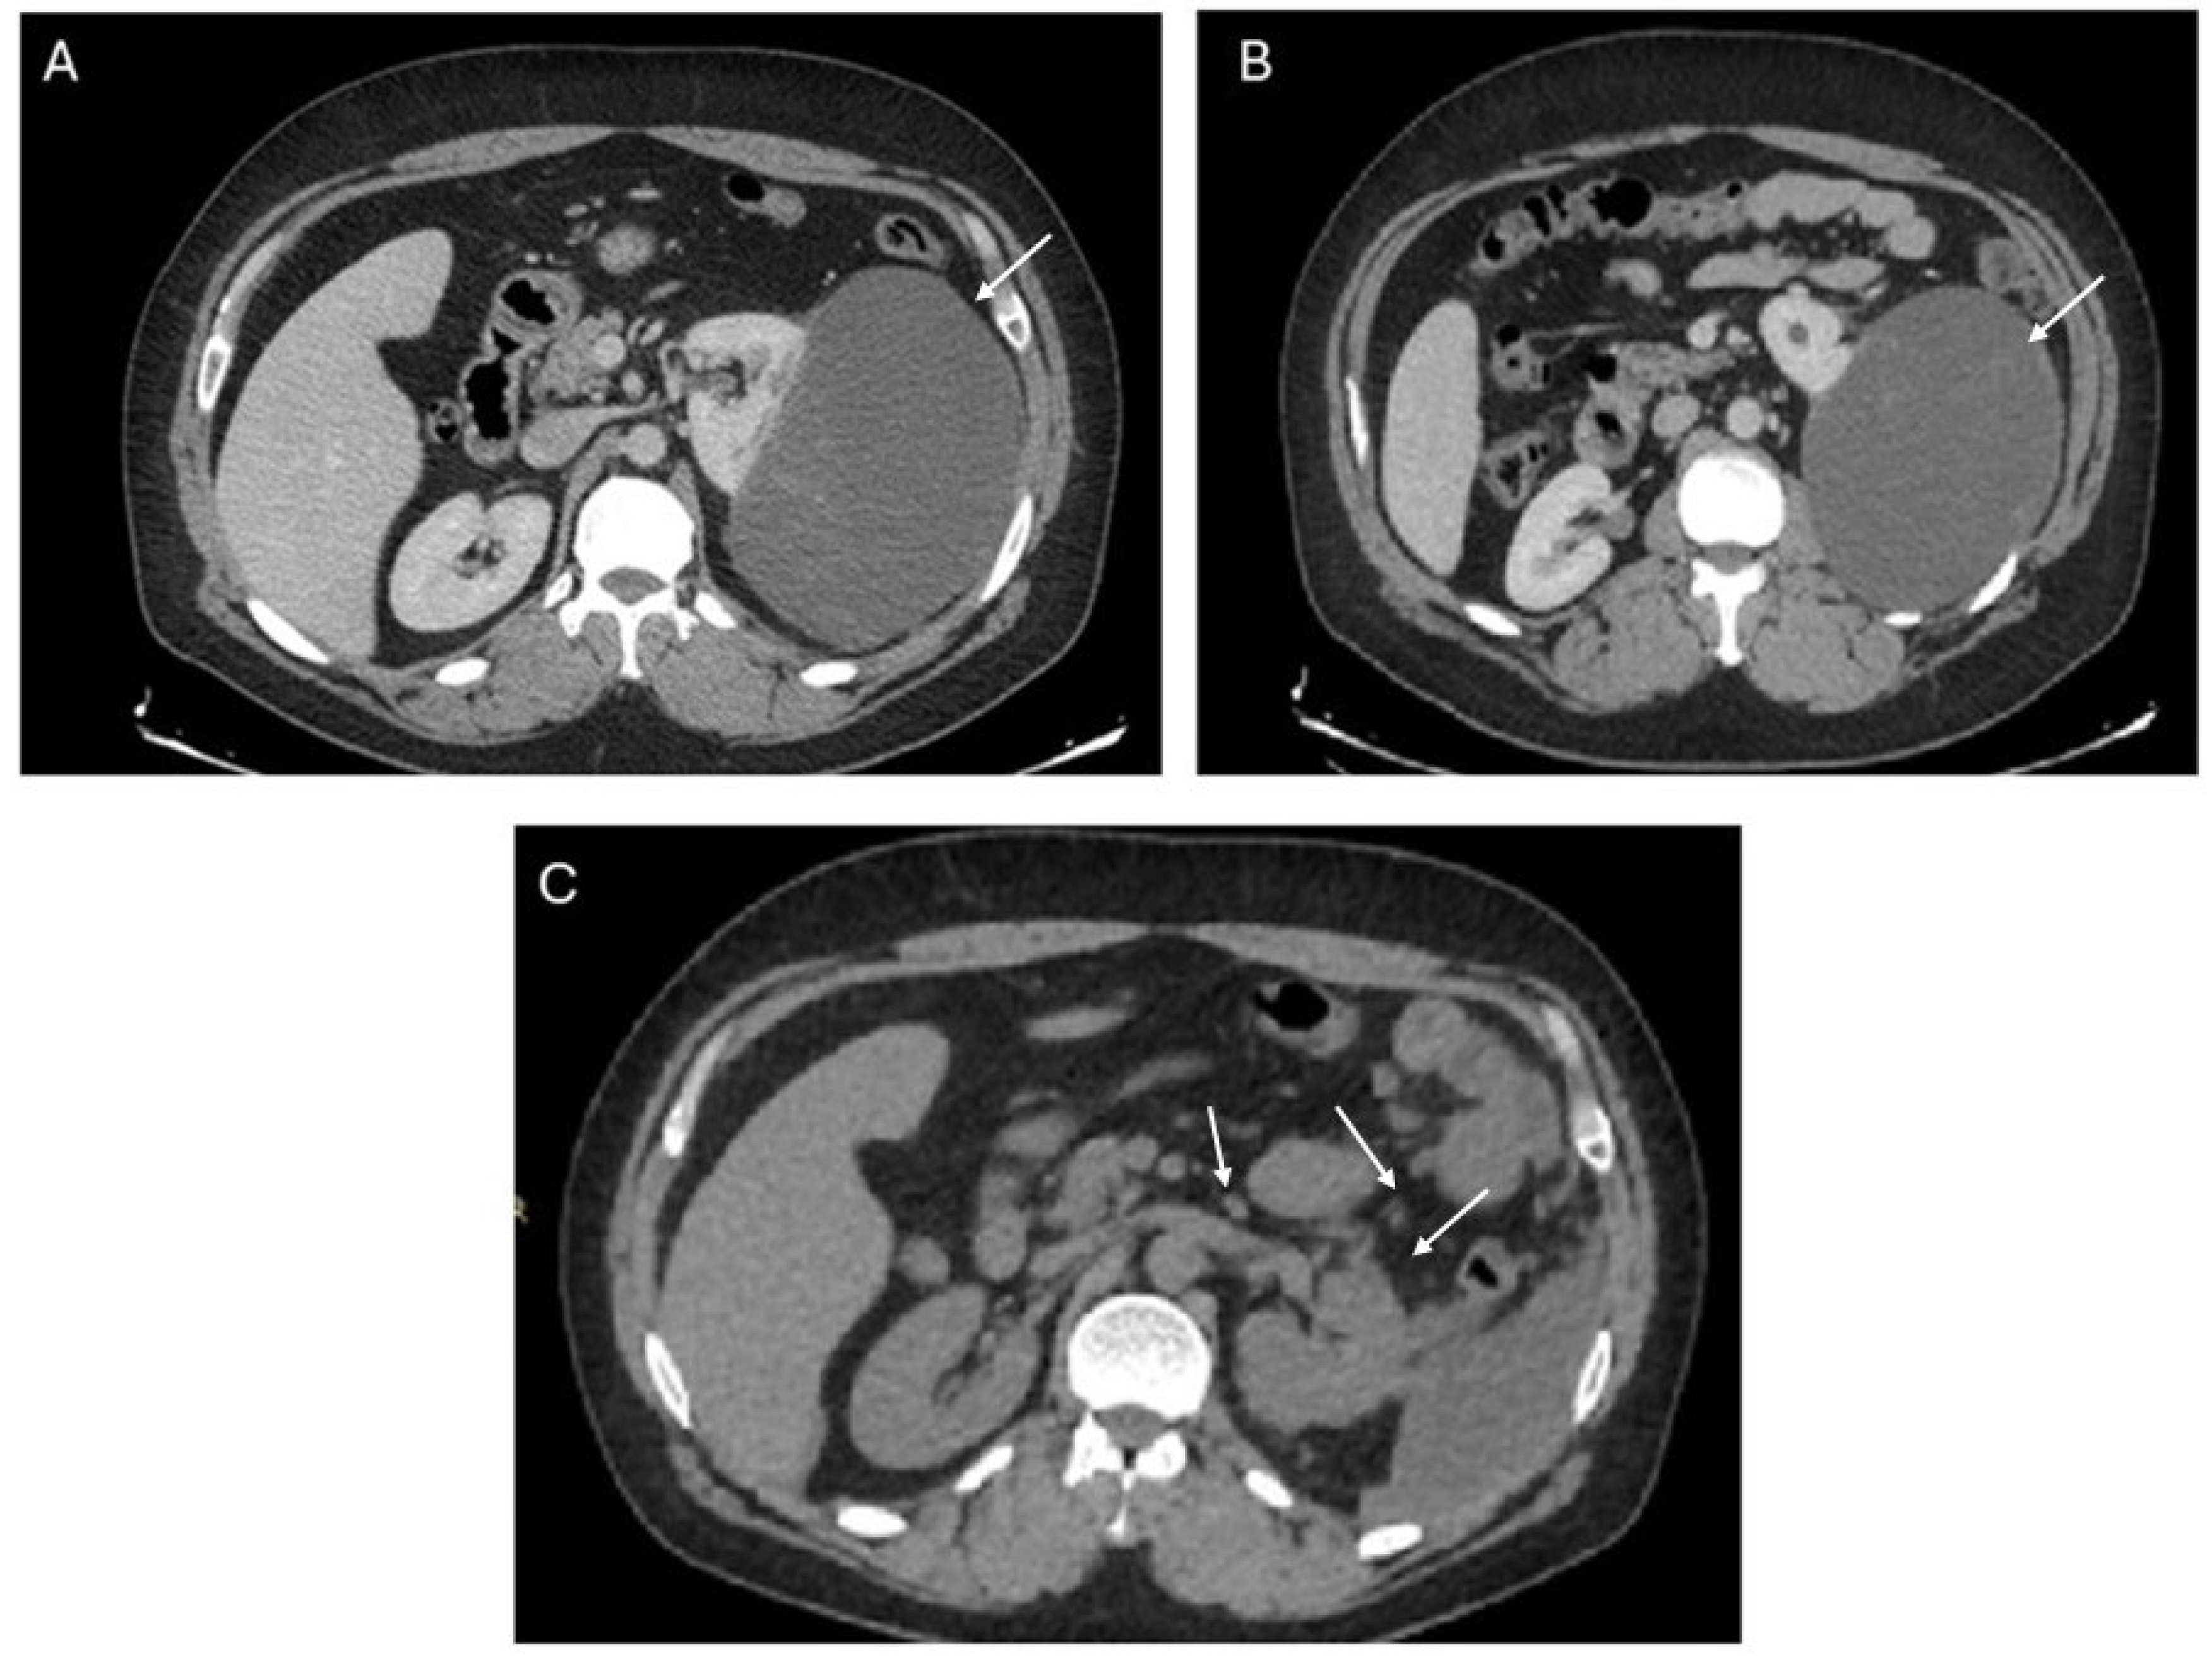

2. Case Report